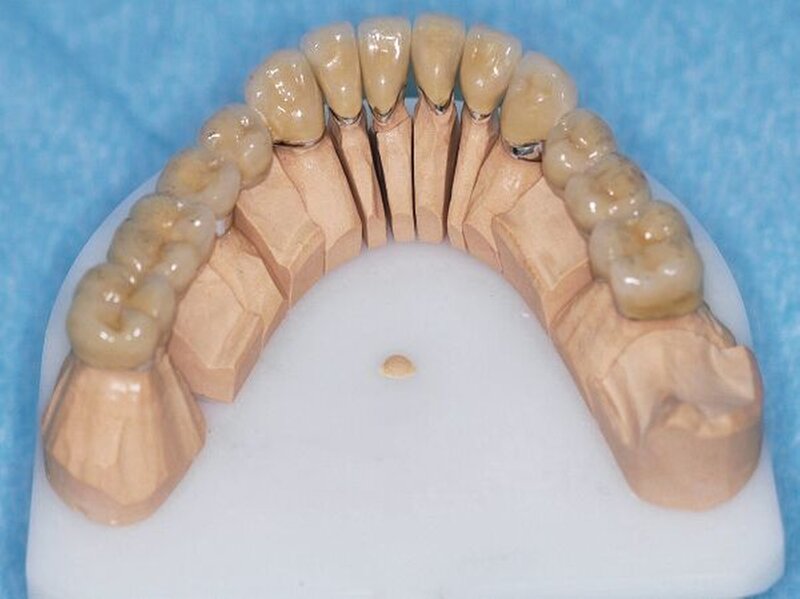

Die Abformungen des OK und des UK erfolgten als Korrekturabformung unter Verwendung eines A-Silikons. Zur Darstellung der subgingival liegenden Präparationsgrenzen wurden mit Adstringentien getränkte, geflochtene Retraktionsfäden in die Sulci aller Zähne eingelegt. Eine adäquate Trocknung der abzuformenden Bereiche wurde durch die Verwendung von Kompressions-Wattekappen, die auf den einzelnen Zähnen platziert wurden, durch Parotispflaster sowie durch eine konstante Absaugung erreicht. Um ein möglichst langes Verarbeitungsintervall zu erzielen, wurde das verwendete Silikon zuvor im Kühlschrank gelagert [Wöstmann et al., 1992; Wöstmann et al., 1999]. Nach erfolgter Abformung wurde ein Gesichtsbogen zur individuellen Übertragung des Oberkiefermodells in den Artikulator angelegt, danach wurden die Provisorien des I- und IV-Quadranten wieder befestigt. Nun wurden partielle interokklusale Registratschlüssel mithilfe eines intraoral anwendbaren Autopolymerisats im Bereich des II- und III-Quadranten angefertigt und beschliffen. In einem zweiten Schritt wurden die Provisorien im I- und IV-Quadranten entfernt und die partiellen interokklusalen Registratschlüssel des II- und III-Quadranten eingesetzt. In dieser Position wurden nun ebenfalls Registratschlüssel im I- und IV-Quadranten angefertigt und beschliffen. Durch dieses Vorgehen war es möglich, die im Rahmen der Registration ermittelte Position – unter Einbeziehung der präparierten Zahnhartsubstanz – auf die Modellsituation des Arbeitsmodells zu übertragen. Abschließend erfolgte die Farbauswahl. Die Arbeitsmodelle wurden mithilfe des zuvor angelegten Gesichtsbogens und der erstellten Registratschlüssel in einen teiljustierbaren Artikulator übertragen. Im Labor erfolgte die Herstellung der Nichtedelmetall-Gerüste der Einzelkronen 22, 32, 31, 41 und 42, die der Brücken 12 bis 21, 35 bis 37 und 43 bis 46 sowie die der Nichtedelmetall- Primärkronen 13, 14, 23 und 24.

In einer weiteren Sitzung erfolgten die Gerüstanproben der angefertigten Restaurationen. Alle Provisorien im Ober- und im Unterkiefer wurden entfernt und die präparierte Zahnhartsubstanz versäubert. Danach wurde die Passgenauigkeit der hergestellten Gerüste am Patienten überprüft. Dies erfolgte unter Verwendung einer Häckchensonde sowie eines niedrigviskösen Silikons. Zudem wurden die mechanische Stabilität, die Friktion und die technische Gestaltung überprüft.